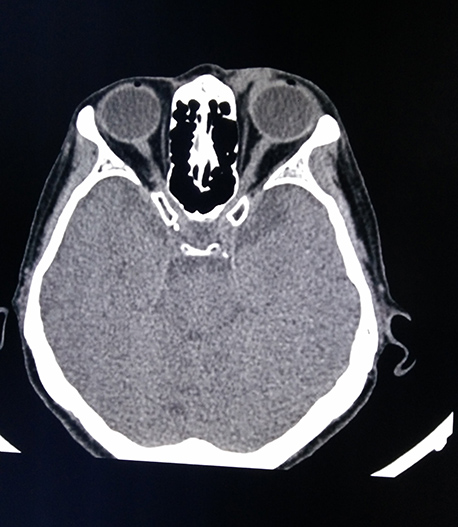

醫(yī)學(xué)影像科現(xiàn)有醫(yī)務(wù)人員15名,其中主任醫(yī)師2名、主治醫(yī)師3名。學(xué)科帶頭人張鐵英主任醫(yī)師、教授,曾任舟山市醫(yī)學(xué)會(huì)放射學(xué)分會(huì)主委,應(yīng)用影像新技術(shù)對(duì)人體各系統(tǒng)進(jìn)行檢查及疾病診斷,尤其是對(duì)神經(jīng)系統(tǒng)、呼吸系統(tǒng)、消化系統(tǒng)、骨關(guān)節(jié)及肌肉系統(tǒng)疾病的影像診斷有較高造詣。醫(yī)學(xué)影像科7×24小時(shí)開放,為醫(yī)院門診、急診及住院患者提供優(yōu)質(zhì)、高效、迅速的影像診療服務(wù)。